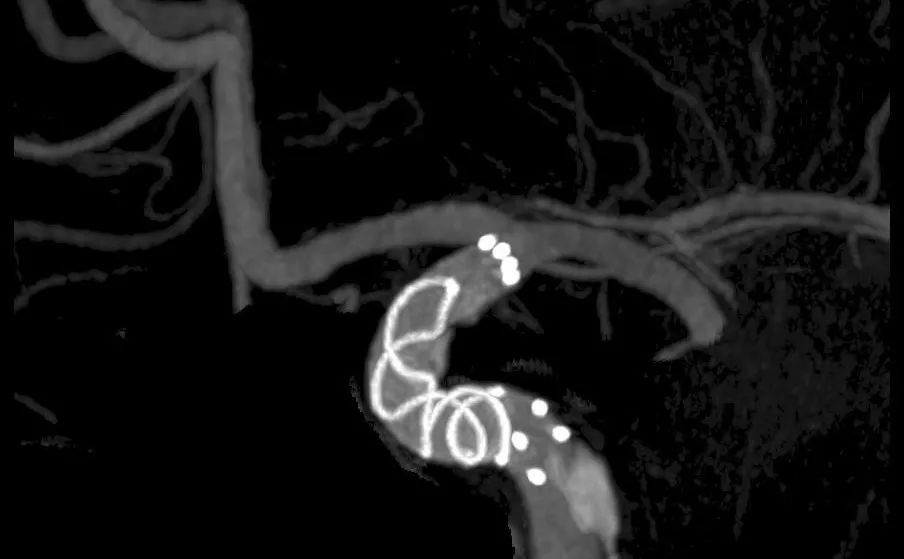

介入科团队在仔细研究影像资料、进行详尽的术前讨论并与家属充分沟通后,制定了周密的手术方案。在麻醉科的密切配合与保障下,手术团队成功为患者实施了微创介入手术。术后影像显示:动脉瘤内造影剂滞留(预示血流隔绝效果良好),支架内血流通畅,支架精细显影并与载瘤血管壁贴合良好。术后患者在神经内科医护团队的精心治疗和护理下顺利康复出院。

动脉瘤密网支架治疗后显示动脉瘤内造影剂滞留,支架内血流通畅

密网支架精细显影,可见支架完全覆盖动脉瘤并与血管壁贴合良好